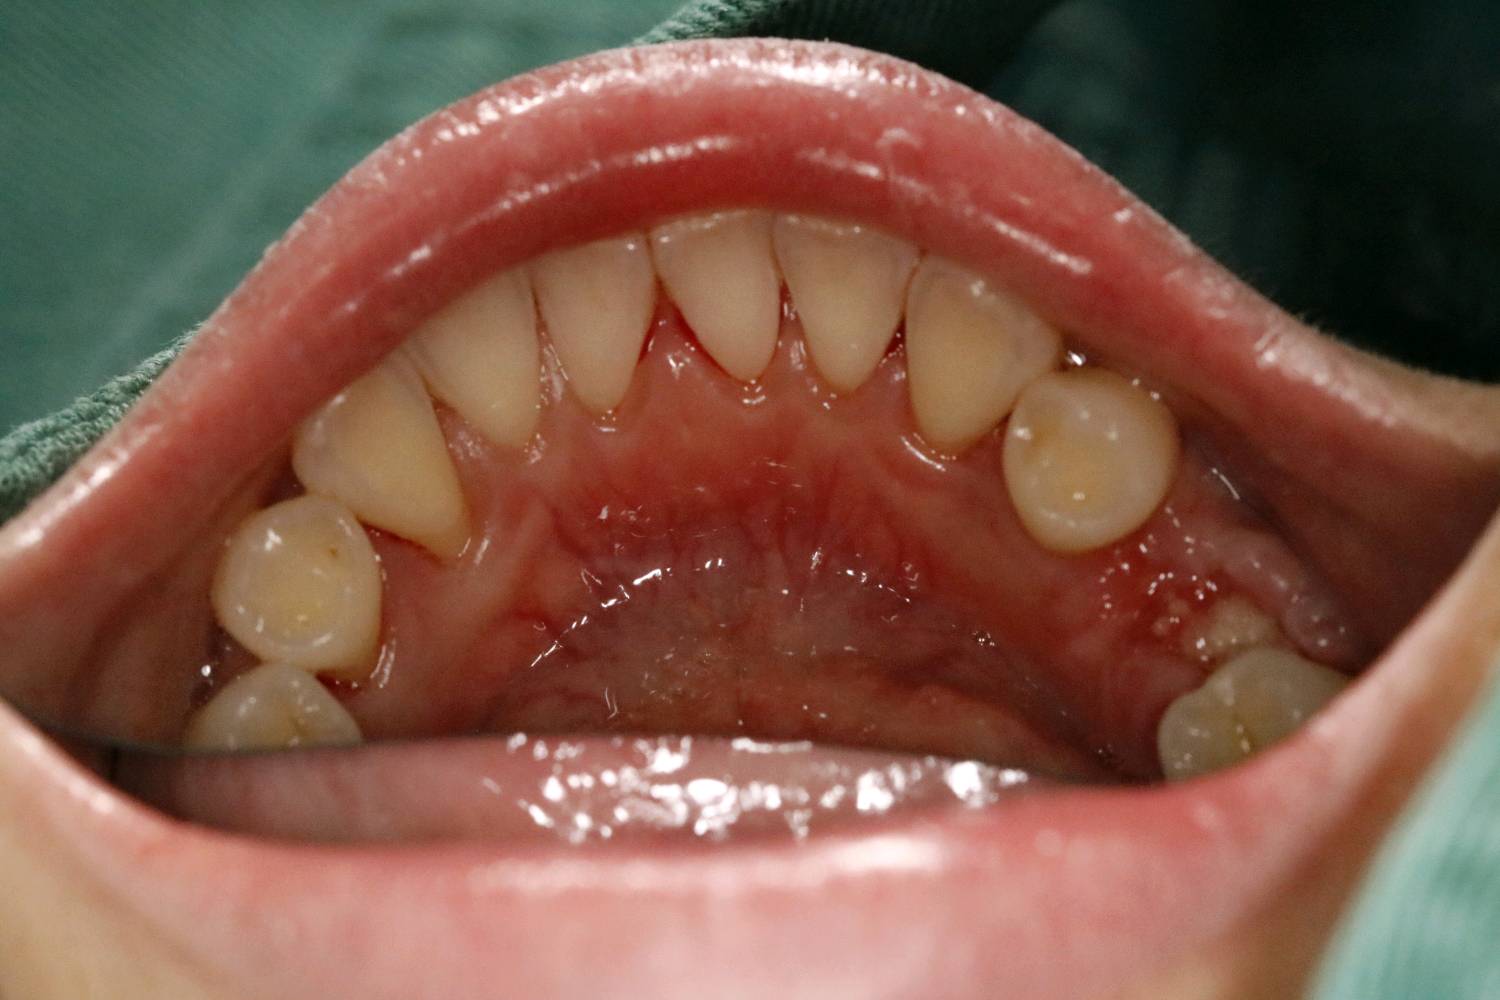

患者女三十岁,35畸形中央尖折断,根尖周炎症感染,导致牙根发育停止,根尖口呈喇叭口状。拔出后搔刮牙槽窝,颊侧骨壁吸收,植入骨粉骨膜。定期复查,将近半年见骨密度良好,骨量充足的条件下,行种植手术。植入3I 4/3*11.5mm的种植体。二期三期如期进行,与今日戴牙,患者满意。